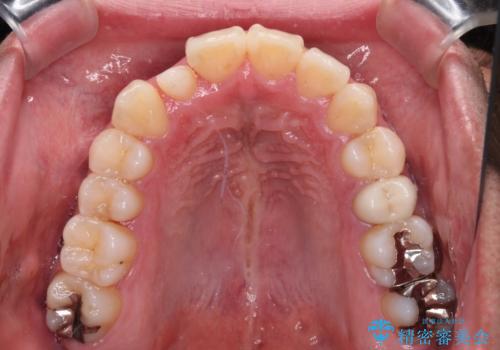

下顎の歯列弓に対して上顎歯列弓がやや小さく、側方の歯を中心にクロスバイトが見受けられました。

後方に隠れていた上顎前歯は矮小歯であるため、矯正治療の途中でオールセラミッククラウンを装着し、左右対称の大きさでの仕上がりを目指すこととしました。

奥歯の咬み合わせは接触が少なく物足りないように見えますが、患者様としては十分に咬むことができるとのことでした。